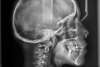

Prognathisme traitée en technique lingual

A-début